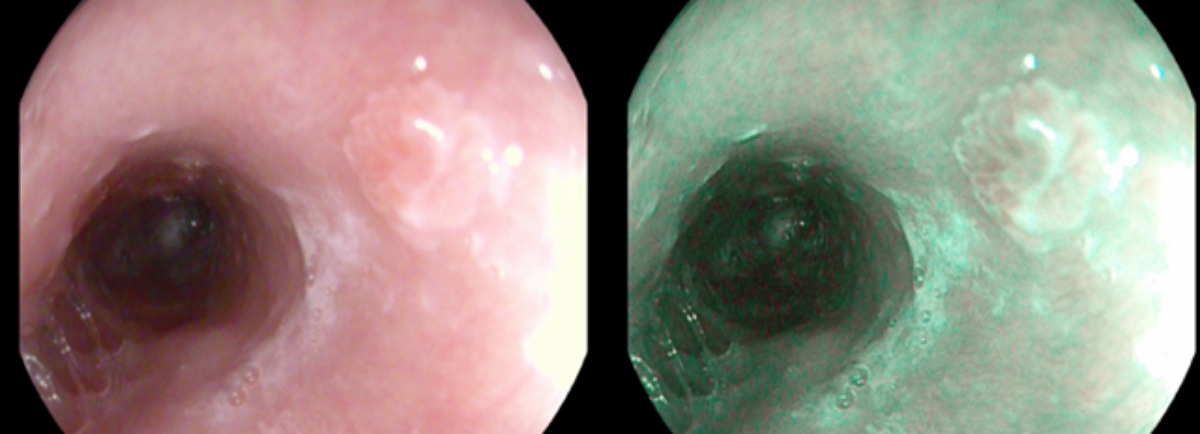

Рис. 1G. Шаг 7. Оценка отдаленных результатов эндоскопического хирургического лечения в режиме узкого спектра с оптическим увеличением в 136 раз с целью исключения рецидивов.

Fig. 1G. Evaluation of long-term results of endoscopic surgical treatment in a narrow spectrum mode with an optical magnification of 136 times in order to exclude relapses.

Более детальная оценка в зоне проведения полипэктомии подтверждает отсутствие рецидива.

Из 48 обследованных пациентов основной группы в 22 случаях под контролем увеличительной хромоэндоскопии были выявлены изменения микроструктуры, ангиоархитектоники, характерные для неопластической перестройки слизистой оболочки пищевода, проведена биопсия, пациенты направлены в стационар для решения вопроса о проведении эндоскопического лечения. 3 пациентам полипэктомия не проведена, в связи с приемом антикоагулянтов и отказом от хирургиечского вмешательства.

23 пациентам проведена эндоскопическая полипэктомия на догоспитальном уровне.